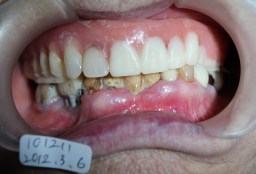

| インプラント植立後4年10カ月後 高齢のため最終補綴を入れずにTEK(仮歯)のままです。 仮歯で状態がよければ2〜10年は持ちます。 壊れた時に最終補物を入れるか再度TEKを作ります。 2016年01月09日撮影(96才) どんなにプラークがついてもインプラント周囲炎は起こりません。 |